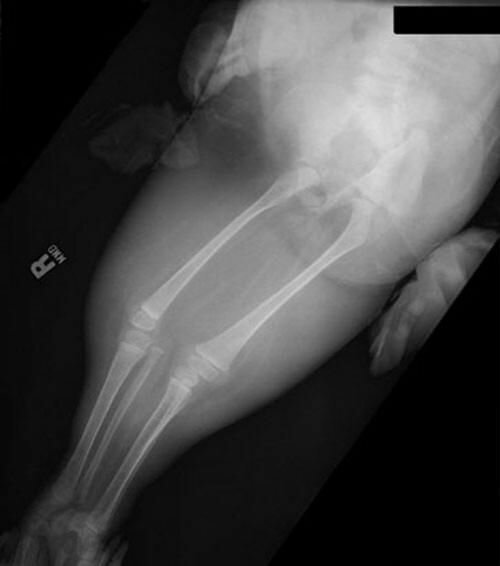

Как передает агентство Associated Press, Шайло Пепин дожила до десяти лет, хотя, когда девочка родилась, медики говорили, что она не протянет и нескольких дней. И небезосновательно: у ребенка была лишь одна почка, работавшая частично, отсутствовали нижняя часть кишечника и половые органы, а ноги были сросшимися и напоминали рыбий хвост.

Причем, были случаи, когда детям, больным сиреномелией или похожими заболеваниями, успешно делали операции по разделению ног. Но случай с Шайло иной: её ноги пересекали крупные кровеносные сосуды, и доктора побоялись разделять их. Девочка, однако, перенесла две операции по пересадке почки, последнюю ей делали в 2007 году.

Сиреномелия (от греч. seiren — сирена, обольстительница, сказочный персонал, и melos — часть тела, конечность) — аномалия развития в форме сращения ног, отсутствия наружных половых органов, неперфорированного ануса и т.?д. Встречается достаточно редко — примерно 1 на 70 тысяч родов, однако подавляющее большинство детей умирает в возрасте от нескольких дней до нескольких месяцев. В настоящее время в мире известны два случая спасения детей с синдромом русалки. Это американка Тифани Йоркс, успешно перенесшая операцию по разделению ног 17 лет назад, и трехлетняя перуанская девочка Милагроз Керрон, последняя операция которой была проведена летом 2006 года. История Шайло уникальна тем, что девочка смогла дожить до такого в данном случае действительно серьезного возраста в своем «первозданном» виде. И самое главное, что все это время она не просто существовала, а училась, общалась и подавала людям пример того, как можно радоваться жизни несмотря ни на что.